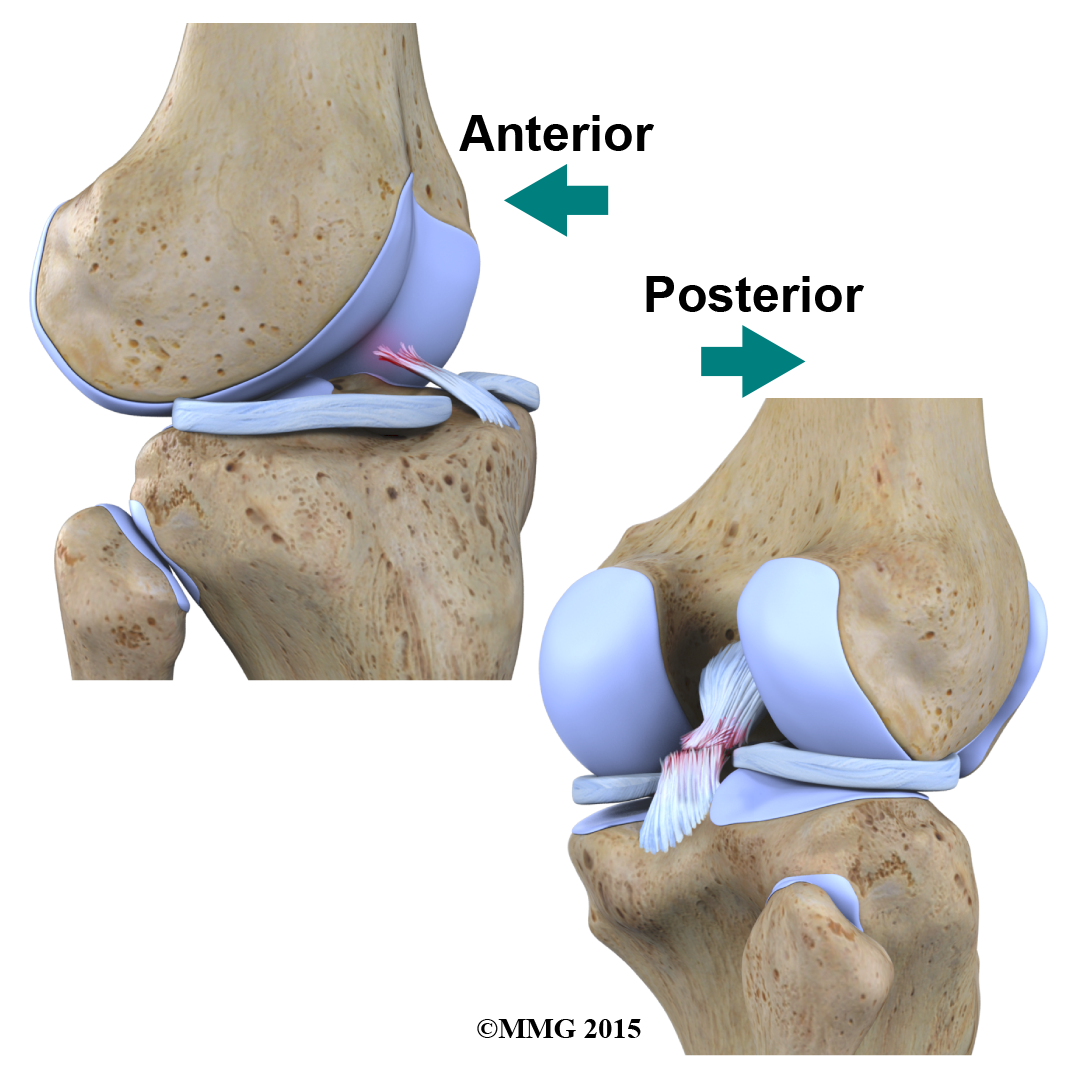

Inside the knee joint, stretch between the femur and the tibia: the anterior cruciate ligament (ACL) in front, and the posterior cruciate ligament (PCL) in back.

The MCL and LCL prevent the knee from moving too far in the side-to-side direction. The ACL and PCL control the front-to-back motion of the knee joint.

The ACL keeps the tibia from sliding too far forward in relation to the femur. The PCL keeps the tibia from sliding too far backward in relation to the femur. Working together, the two cruciate ligaments control the back-and-forth motion of the knee. The ligaments, all taken together, are the most important structures controlling stability of the knee.